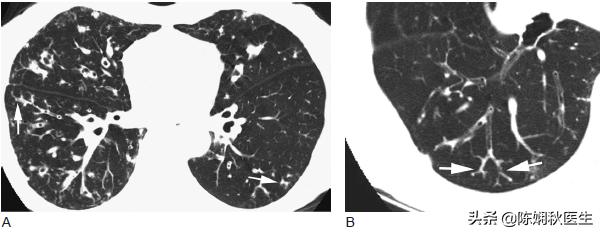

其实支气管扩张是一种并不少见的慢性肺部疾病,强调一下,它不是急性的毛病,不是我们通常所说的“肺炎”(来得快,好的也快,好了就能彻底消失了)。支气管扩张,它形成的原因一部分是先天性的因素,另一部分是因为肺部感染以后,支气管形成了持久性的扩张,并且支气管壁遭到了永久性的破坏,形成了一种肺部的慢性炎症。通常会表现为慢性的咳嗽,大量的咳痰,有时会伴有咯血。也有一些病人症状不典型,最终需要以肺部CT的影像表现来判断。